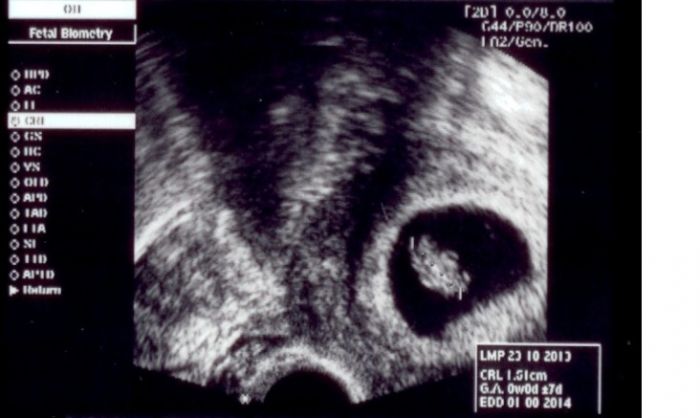

A tady je moje zelvicka